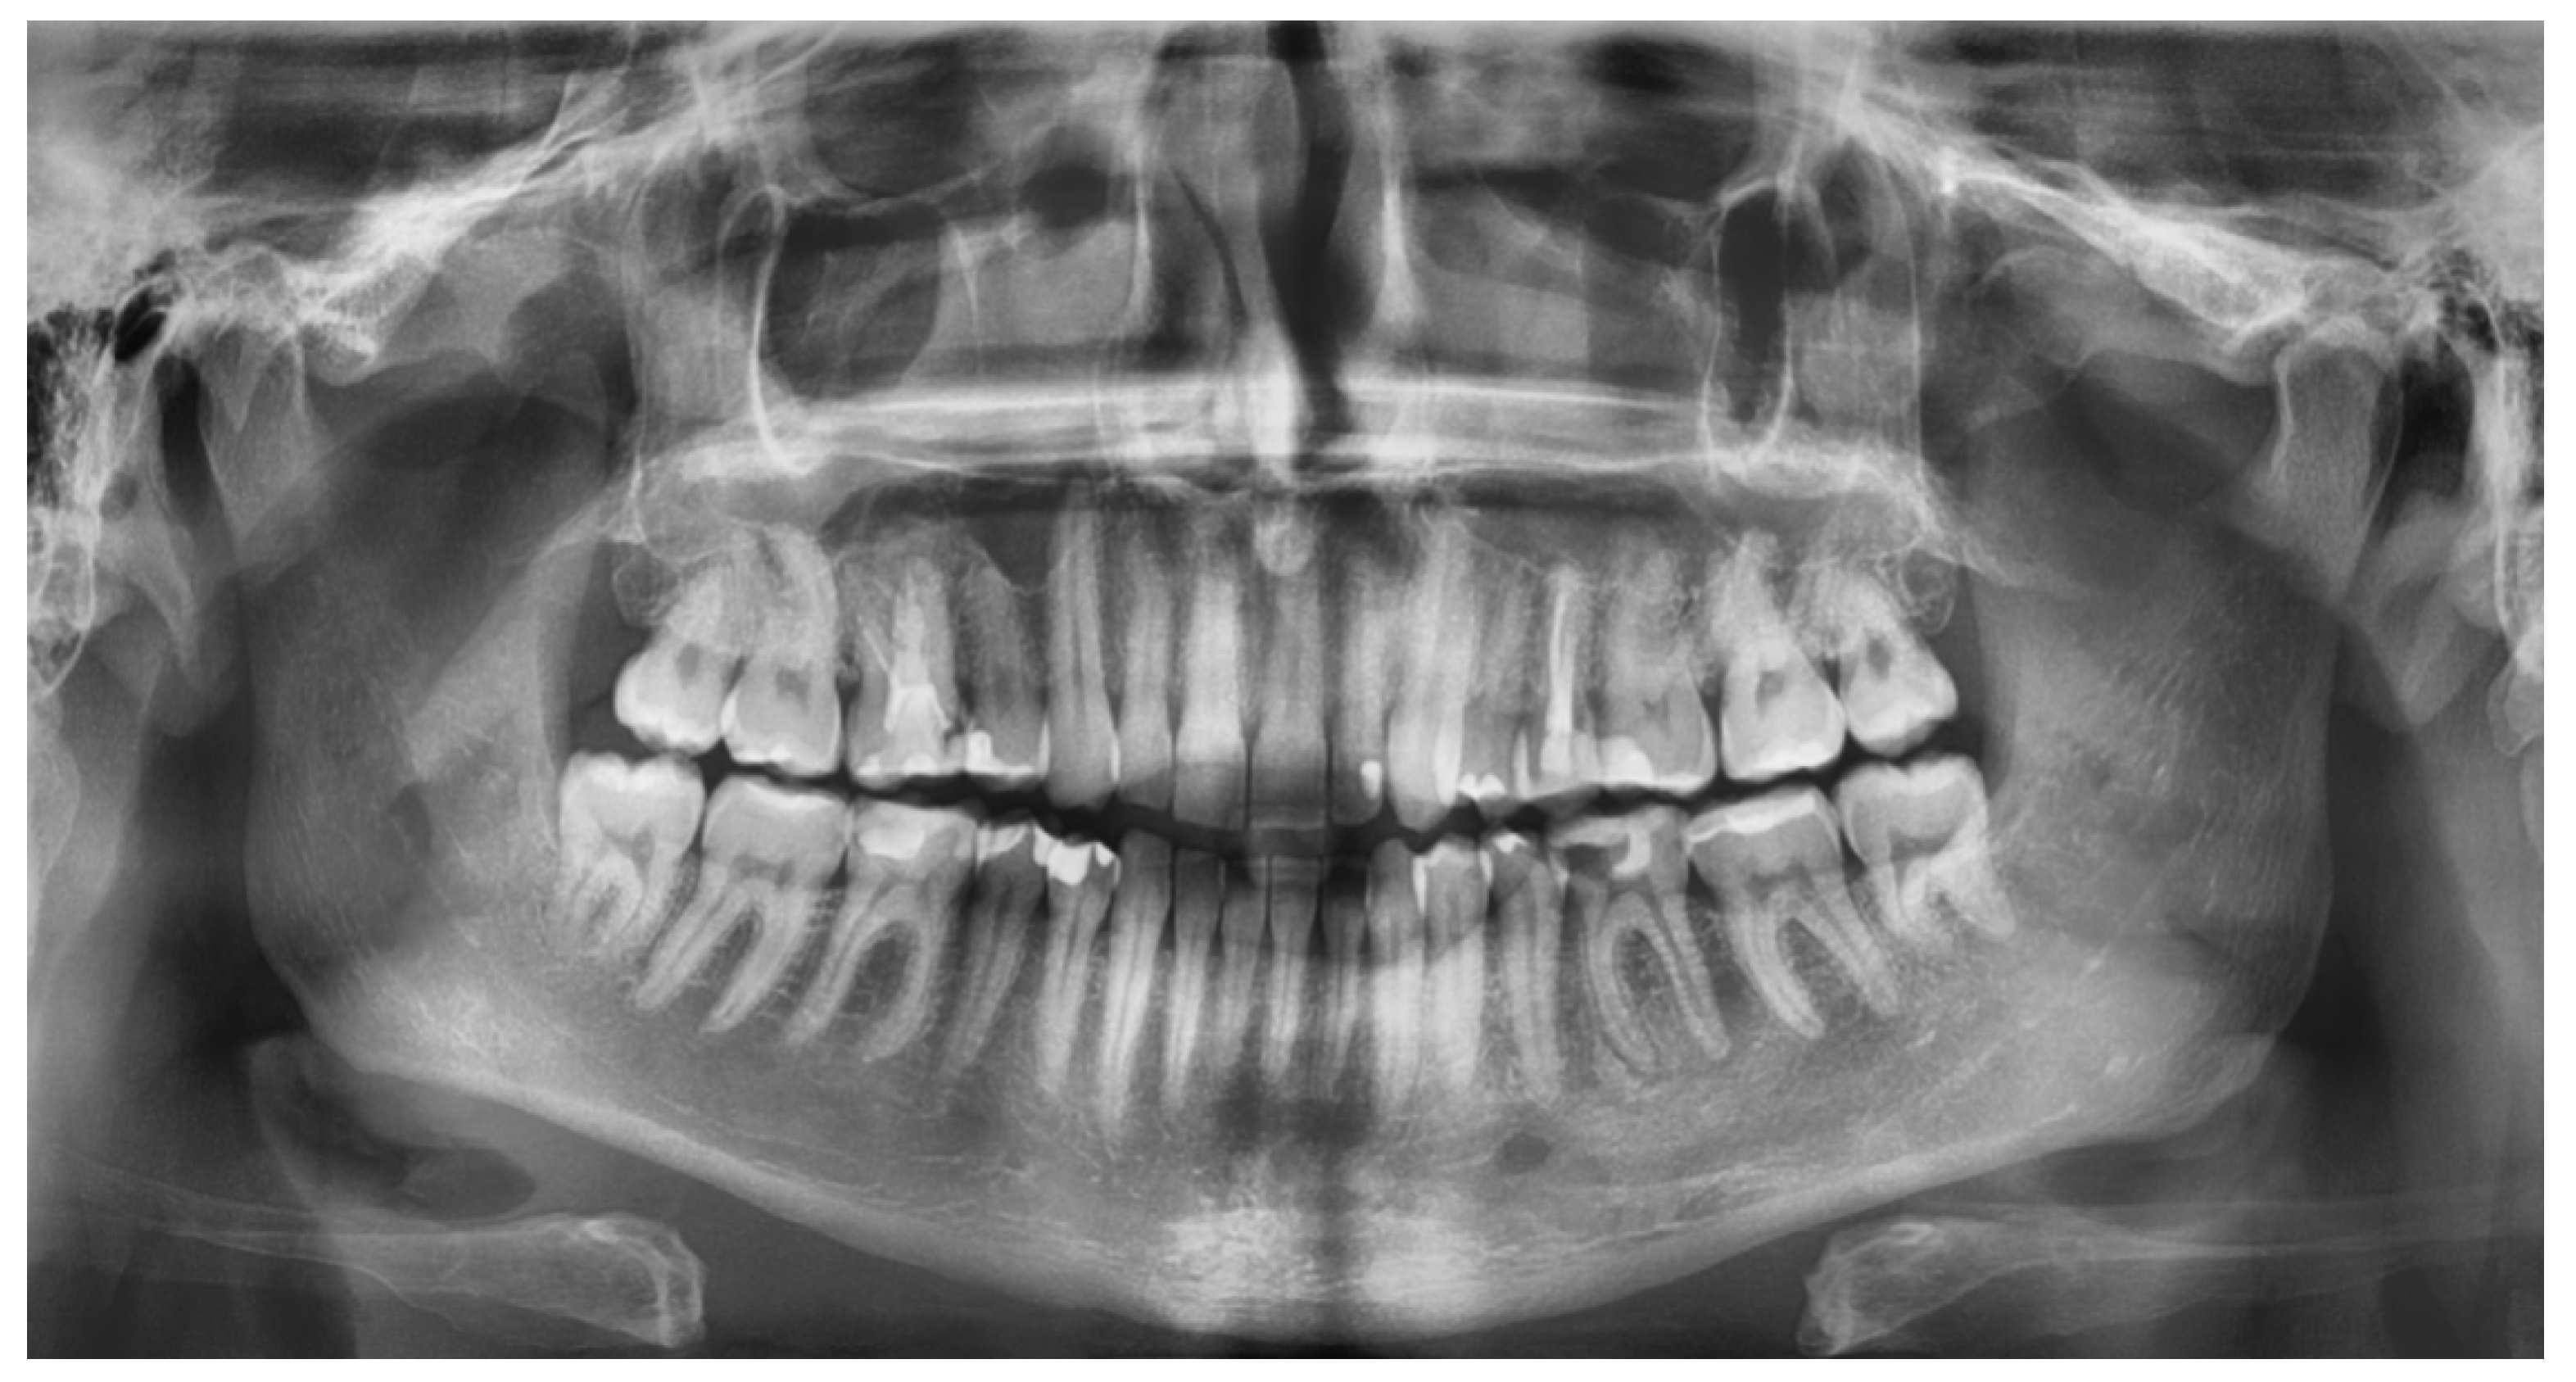

2.2. Radiological Study Protocol

- Maćkowiak, P.; Kaczmarek, E.; Kulczyk, T. Cortical width measurement based on panoramic radiographs using computer-aided system. In Bio-Informatic Systems, Processing and Applications; Abginya, J., Custovic, E., Whittingen, J., Eds.; River Publishers: Aalborg, Denmark, 2013; Volume 2.1, pp. 169–190. [Google Scholar]

- Devlin, H.; Karayianni, K.; Mitsea, A.; Jacobs, R.; Lindh, C.; van derStelt, P.; Marjanovic, E.; Adams, J.; Pavitt, S.; Horner, K. Diagnosing osteoporosis by using dental panoramic radiographs: The OSTEODENT project. Oral Surg. Oral Med. Oral Pathol. Oral Radiol. Endodontol. 2007, 104, 821–828. [Google Scholar] [CrossRef]

- Karayianni, K.; Horner, K.; Mitsea, A.; Berkas, L.; Mastoris, M.; Jacobs, R.; Linfh, C.; van der Stelt, P.; Harrison, E.; Adams, J.E.; et al. Accuracy in osteoporosis diagnosis of a combination of mandibular cortical width measurement on dental panoramic radiographs and a clinical risk index (OSIRIS): The OSTEODENT project. Bone 2007, 40, 223–229. [Google Scholar] [CrossRef]

- Horner, K.; Karayianni, K.; Mitsea, A.; Berkas, L.; Mastoris, M.; Jacobs, R.; Lindh, C.; van der Stelt, P.; Marjanovic, E.; Adams, J.; et al. The mandibular cortex on radiographs as a tool for osteoporosis risk assessment: The OSTEODENT Project. J. Clin. Densitom. 2007, 10, 138–146. [Google Scholar] [CrossRef]